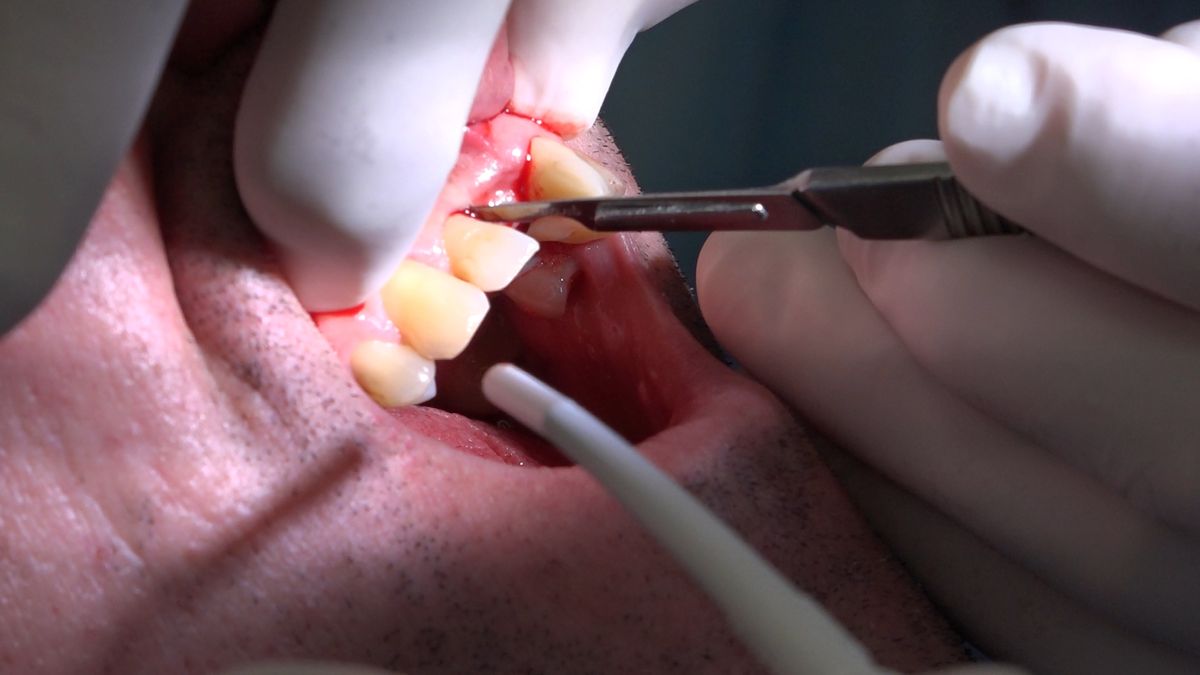

Practiculum Implantologii – Sezon VIIB, sesja 7, dzień 2